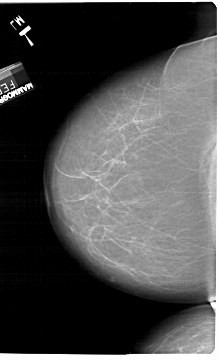

ics_version 1.0 filename A-1494-1 DATE_OF_STUDY 7 2 1994 PATIENT_AGE 61 FILM FILM_TYPE REGULAR DENSITY 2 DATE_DIGITIZED 25 8 1998 DIGITIZER HOWTEK 43.5 SEQUENCE LEFT_CC LINES 6871 PIXELS_PER_LINE 4141 BITS_PER_PIXEL 12 RESOLUTION 43.5 NON_OVERLAY LEFT_MLO LINES 6316 PIXELS_PER_LINE 4006 BITS_PER_PIXEL 12 RESOLUTION 43.5 NON_OVERLAY RIGHT_CC LINES 6436 PIXELS_PER_LINE 4126 BITS_PER_PIXEL 12 RESOLUTION 43.5 OVERLAY RIGHT_MLO LINES 6616 PIXELS_PER_LINE 4126 BITS_PER_PIXEL 12 RESOLUTION 43.5 OVERLAY |